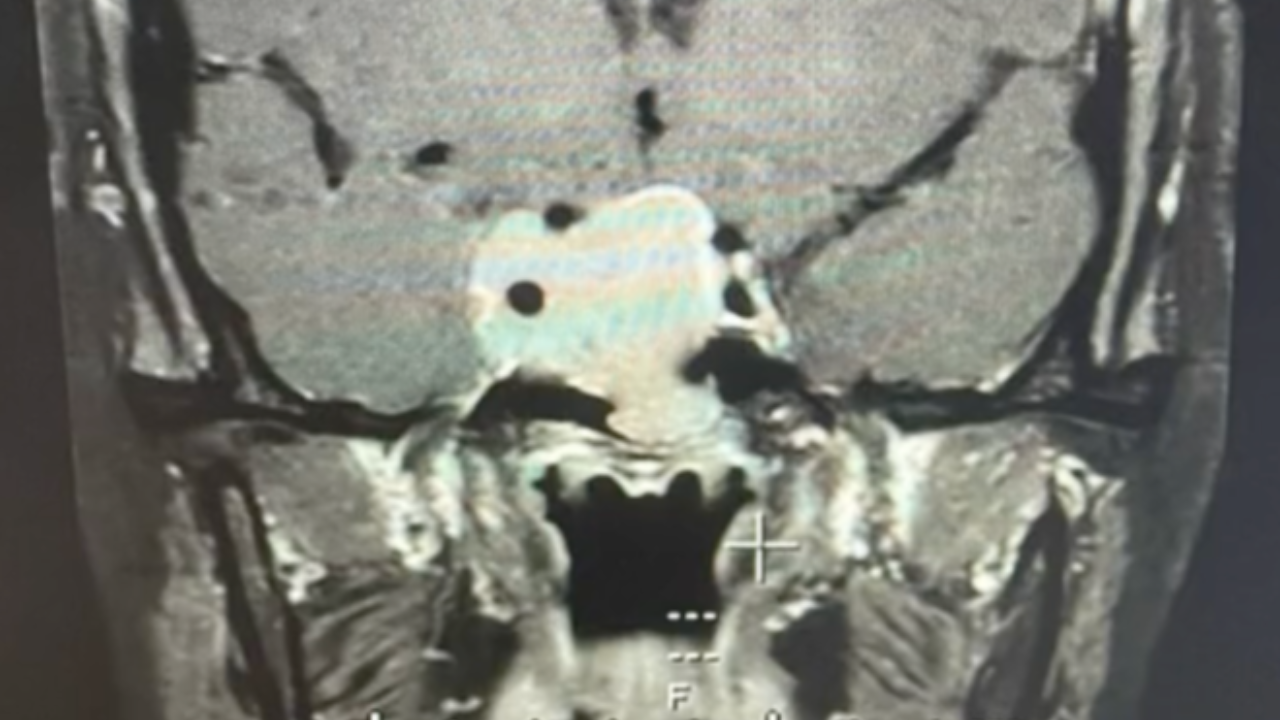

ดังนั้นการที่ค่าตัวนี้สูงแปลว่า ต้องมีอะไรผิดปกติ จึงไปค้นหาดูว่าผิดปกติจากอะไรได้บ้าง ซึ่งเขาเขียนว่า เป็นไปได้ว่าจะมีเนื้องอกต่อมใต้สมอง ซึ่งจะมีเคสว่าถ้าเป็นเนื้องอกต่อมใต้สมอง ตัวโปรแลคตินจะสูงมาก คนทั่วไปจะอยู่ที่ 17 แต่ของเราตรวจได้ประมาณ 26-40 กว่า ซึ่งไม่สูงมาก ซึ่งคุณหมอให้ทำ MRI ผลออกมาว่า เป็นเนื้องอกต่อมใต้สมอง 3 เซนติเมตร และได้เข้าสู่ขั้นตอนการรักษา.